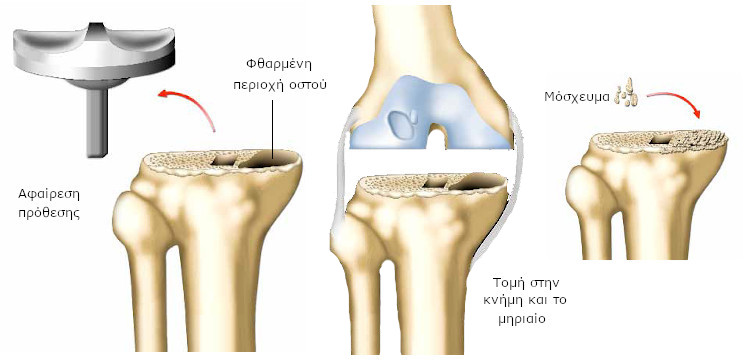

Εάν δεν υπάρχει λοίμωξη, ο χειρουργός μπορεί να αντικαταστήσει το σύνολο ή τμήμα της πρόθεσης. Αν ωστόσο, υπάρχει λοίμωξη, πρέπει να αφαιρεθεί το σύνολο της πρόθεσης, καθώς επίσης και περιοχές που έχουν προσβληθεί από μικρόβια.

Ίσως χρειαστεί να αποκατασταθούν και περιοχές του οστού, που έχουν υποστεί σοβαρή βλάβη, με οστό που λαμβάνεται από άλλο σημείο του σώματός σας (μόσχευμα), ή προέρχεται από άλλο άτομο. Μπορεί επίσης να χρησιμοποιηθούν τεχνητά υλικά, ειδικά για αυτή την περίπτωση.

Ο χειρουργός αφαιρεί την πρόθεση και καθαρίζει την περιοχή (θραύσματα οστού, πιθανώς τσιμέντου, κτλ.)

Εάν πρόκειται για σηπτική χαλάρωση, πρέπει επίσης να αφαιρέσει όλες τις περιοχές που έχουν προσβληθεί από μικρόβια.

Είναι το πιο χρονοβόρο μέρος της επέμβασης. Στη συνέχεια, προετοιμάζει το οστό για την τοποθέτηση της νέας πρόθεσης. «Κόβει» το οστό της κνήμης και του μηριαίου, που έχει φθαρεί.

Ο χειρουργός μπορεί να χρειαστεί να προβεί σε επιπλέον ενέργειες. Ο στυλεός περνά από το κέντρο του μηριαίου και της κνήμης και σταθεροποιεί την πρόθεση. Εφόσον το οστό έχει φθαρεί, είναι πιθανό να χρησιμοποιηθούν σφήνες για να συμπληρωθούν τα κενά.

Εάν οι βλάβες στο οστό είναι σοβαρές, ιδιαίτερα στην περίπτωση σηπτικής χαλάρωσης, μπορεί να χρειαστεί ανοικοδόμηση οστού:

είτε χρησιμοποιώντας τεχνητό υλικό (οστικό υποκατάστατο) για την αντικατάσταση του οστού,

είτε με οστό που λαμβάνεται από άλλο σημείο του σώματός σας (αυτόλογο μόσχευμα) ή από άλλο άτομο (τράπεζα μοσχευμάτων).

Το οστό αυτό (ή το τεχνητό οστό) τοποθετείται στις φθαρμένες περιοχές. Σταδιακά, ενώνεται με το υγιές οστό του ασθενή. Πρόκειται για μόσχευμα. Η διαδικασία για τη λήψη και τοποθέτηση οστικού μοσχεύματος καθορίζεται από αυστηρό νομοθετικό πλαίσιο.